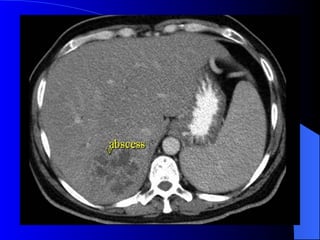

Absceso hepático amebiano

Absceso hepático amebiano Serologia para ameba positiva. Leucocitosis Fosfatasa alcalina elevada. Hipoalbuminemia

Tratamiento Metronidazol. IV Drenaje percutaneo Drenaje quirúrgico en caso de ruptura, puede drenarse  espontaneamente a  cavidad peritoneal, pericardio, pleura-